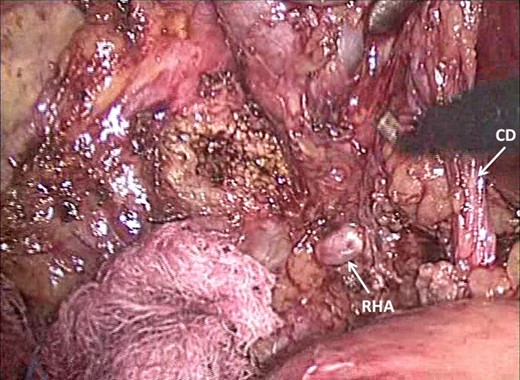

Dissection has presented Rouviere's sulcus (open-type) with the right hepatic artery (RHA) visible superficially. The close relationship to the CD in Calot's triangle is demonstrated.

We do agree that these operations tend to be technically difficult because there is usually significant scarring and anatomic distortion at the gallbladder bed [2–9]. However, careful and patient dissection can allow the procedure to be completed safely. Even in our setting where resources are limited, we were able to perform the dissection safely using only ‘hot scissors’ without the need for ultrasonic dissectors or any specialized equipment. During dissection, it is important for the surgeon to be aware of important anatomic landmarks, such as Rouviere's sulcus. This can prevent inadvertent injury to the right hepatic pedicle structures that may present themselves in the surgical field during dissection of Calot's triangle. We also advocate dissection to approach the gallbladder remnant from the right side in order to avoid the difficult dissection near the hepatic hilum. These principles were clearly demonstrated in this case where the right hepatic structures presented themselves in the surgical field during dissection of Calot's triangle while approaching the gallbladder from its right side.